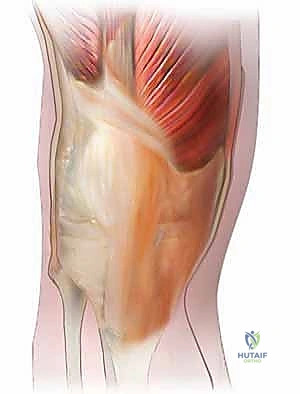

الخطوة الثانية: الفتح الجراحي المتقدم (Extensile Exposure)

الركبة المتصلبة تكون قاسية جداً ويصعب كشفها بالطرق العادية. يستخدم الدكتور هطيف تقنيات جراحية دقيقة لحماية الوتر الرضفي من التمزق، وقد يتطلب الأمر إجراء قص عظمي بسيط في نتوء الساق (Tibial Tubercle Osteotomy) أو قص في وتر العضلة الرباعية (Quad Snip) للوصول الآمن للمفصل.

الخطوة الخامسة: إعادة ضبط الفجوات وتوازن الأربطة (Balancing)

هذه هي "الهندسة الحقيقية" في العملية. يقوم الجراح بقياس الفجوات في وضع الثني والفرد، وضبطها لتكون متساوية، مع التأكد من أن الأربطة الجانبية ليست مشدودة جداً ولا مرتخية جداً.